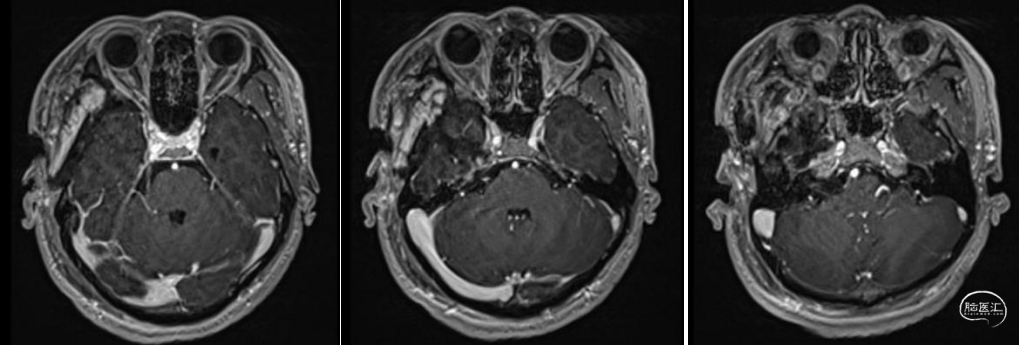

术前影像学资料

三叉神经鞘瘤的影像学可分型为:中颅窝型(位于鞍旁,常沿鞍内生长,岩骨尖部骨质吸收,海绵窦、颞叶受压推挤),后颅窝型(多位于桥小脑角区域,瘤体主要位于硬膜下,膨胀性生长),中后颅窝型(沿三叉神经走形,骑跨中后颅窝,表现为典型的“哑铃状”生长,常伴岩尖骨质破坏),颞下窝、翼腭窝型(向颅中窝、颞下窝、翼腭窝生长,伴有圆孔、卵圆孔扩大),眼眶型。

三叉神经鞘瘤常有明确包膜,对于中颅窝型三叉神经鞘瘤,其向内侧挤压海绵窦,但两者之间存在膜性边界,因此,单纯海绵窦神经鞘瘤可以理解为硬膜外病变,经硬膜外入路解剖清晰、操作简洁、脑损伤发生率低、能较好控制海绵窦出血(“第十期:扩大中颅窝入路经硬膜外切除三叉神经鞘瘤”我科已有相应病例汇报)。但本例肿瘤起源于三叉神经脑干端,从后颅窝生长至中颅窝(海绵窦旁),从圆孔向下生长至翼腭窝。中后颅窝肿瘤大部位于硬膜下,海绵窦侧壁、岩尖部位的肿瘤体积相对较小,故手术入路选择经硬膜下切除中后颅窝病变,可清晰辨认三叉神经主体及分支,且能够更加从容处理海绵窦侧壁肿瘤。而翼腭窝为硬膜外病变,故经硬膜外入路切除翼腭窝区域肿瘤。